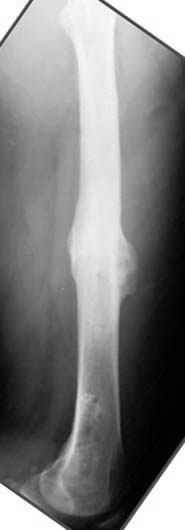

Несколько снимков из моей коллекции, чтобы разьяснить, почему мы до сих пор делаем различные варианты остеотомии.

На рисунке N1 предоперационный план лечения ложного сустава шейки бедра- линия ложного сустава, угол и направление введения импланта, клиновидная остеотомия в градусах и миллиметрах, второй снимок после коррекции, расчет, на сколько удлиняется конечность и размеры импланта;

N3 рисунок окончательный снимок, после операции моя рентгенограмма должен выглядеть примерно как эта картина. На N4 снимке клин перед удалением; N5 послеоперации 3 нед.; N6 окончательная рентгенограмма.

(доложен в Ст. Петербурге 2003 и в Москве 2004)

варус при проксимальном отделе 95 градусной пластиной.